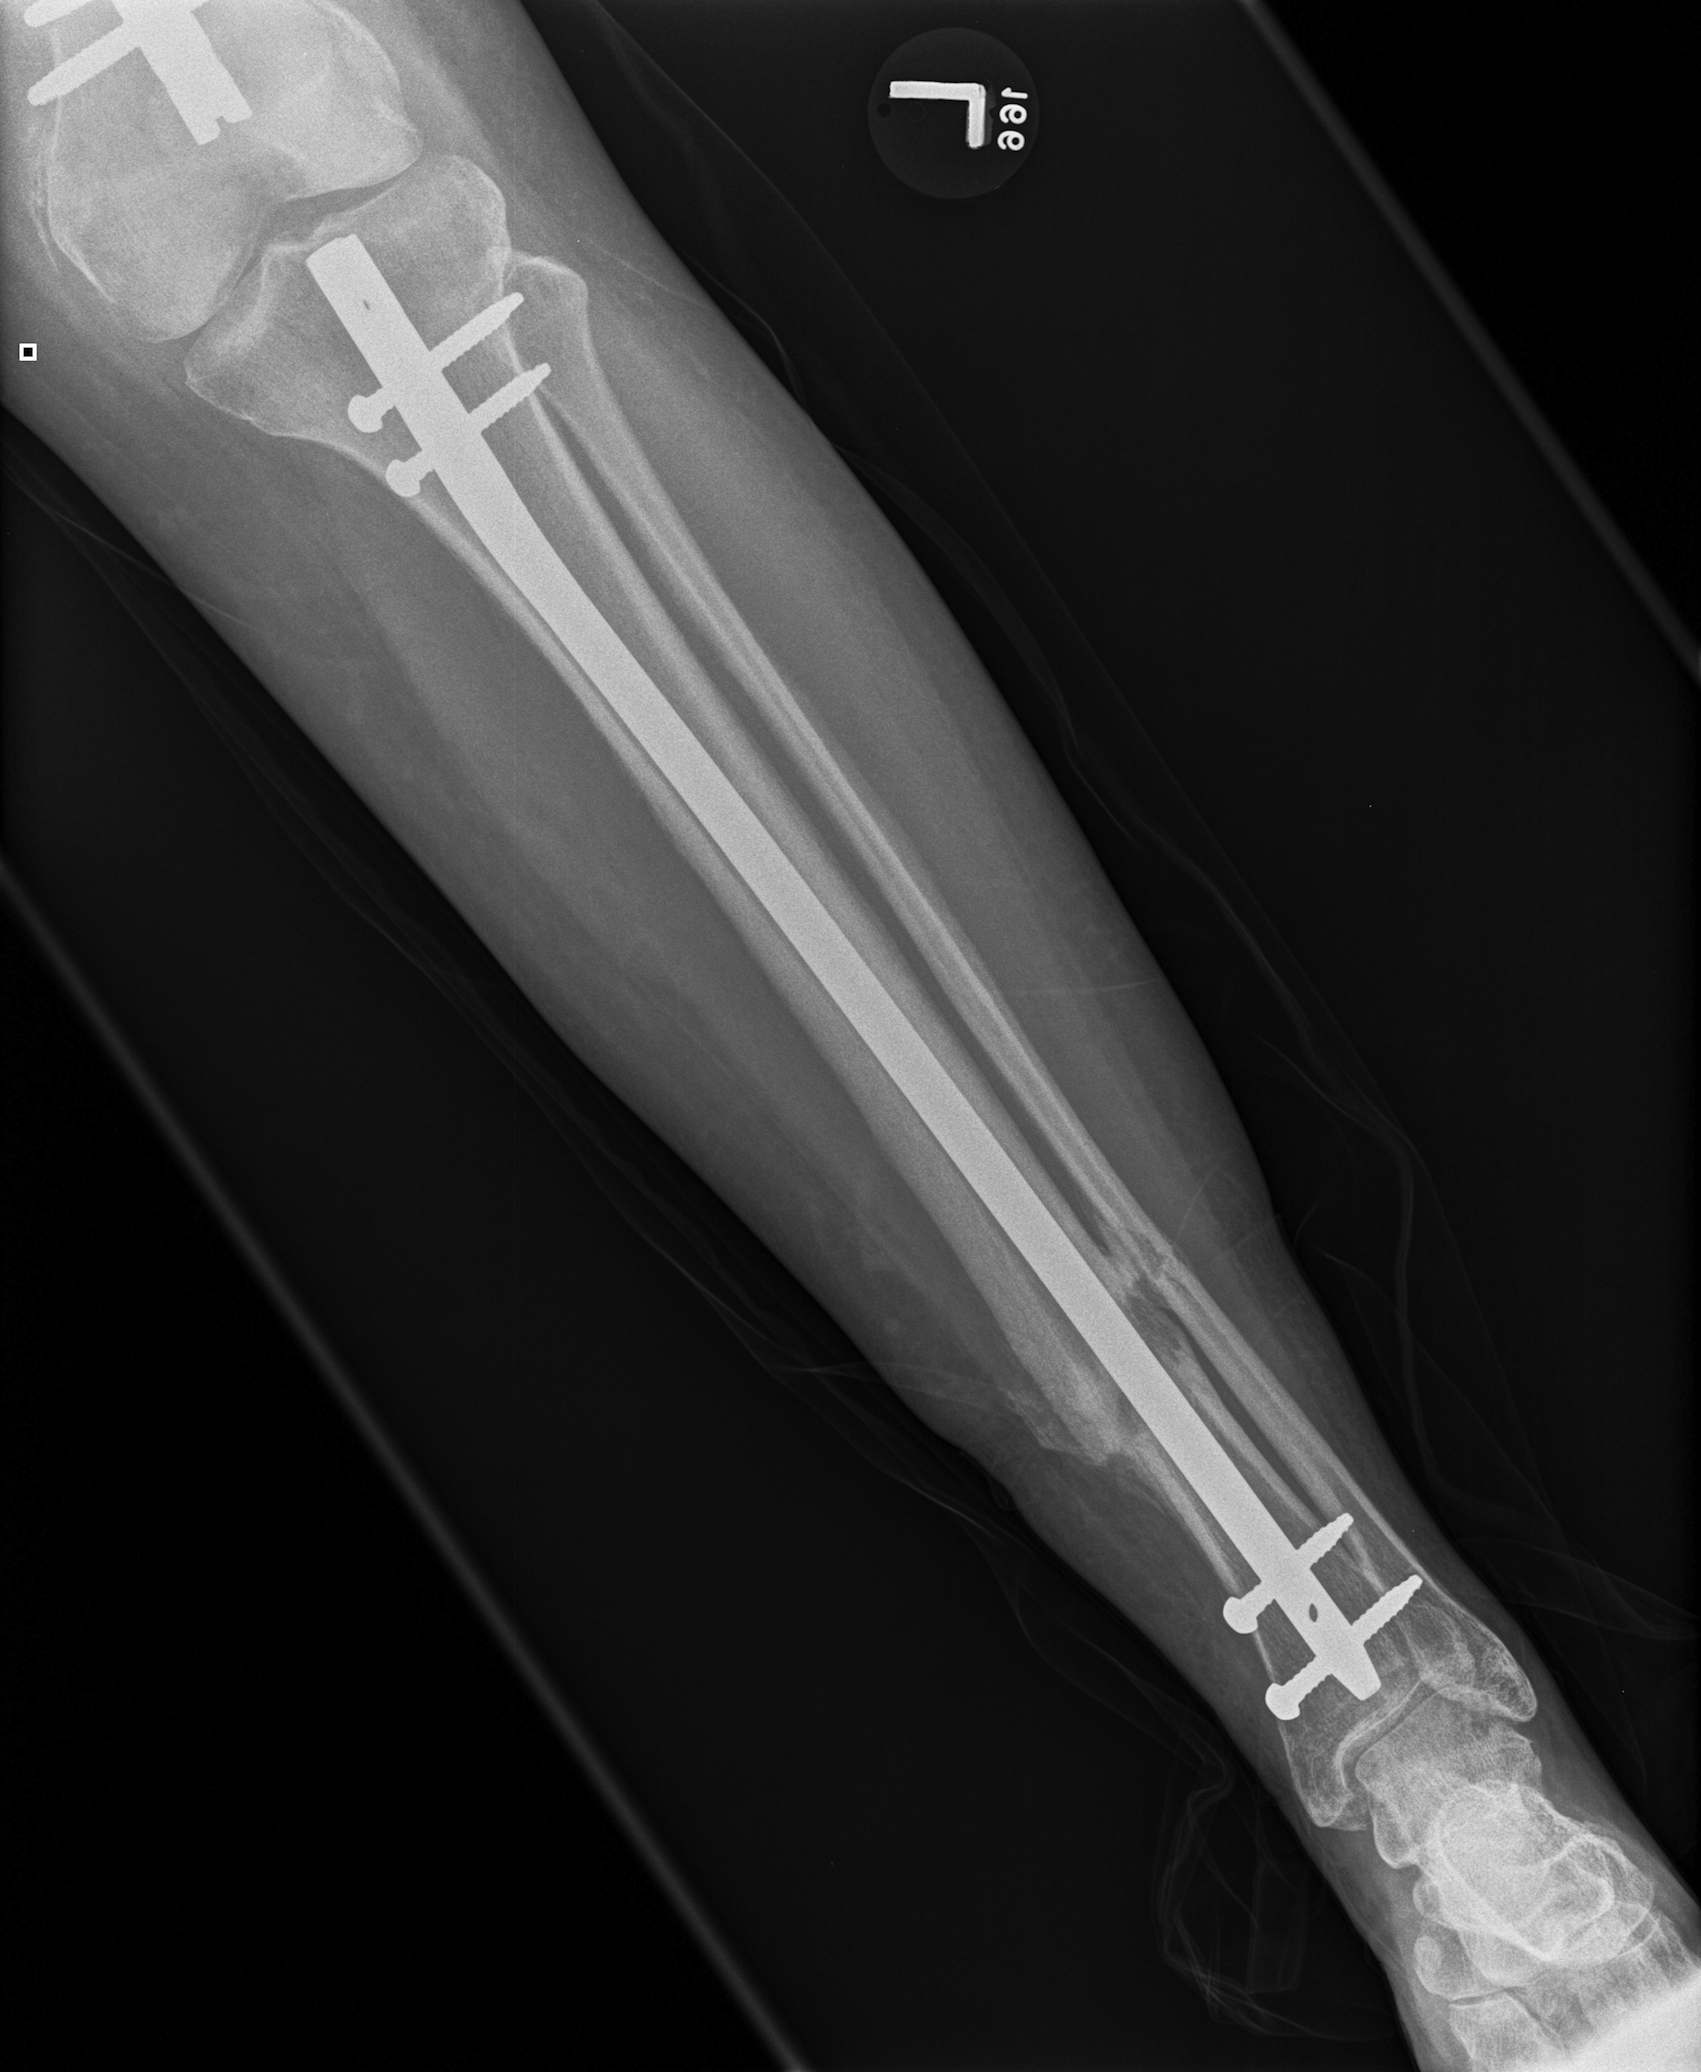

Floating Knee

Ipsilateral femur + tibial fracture

1. Floating Knee

Single incision at knee

- retrograde femoral nail

- tibial IMN if appropriate

High complication rates including non union / malunion, knee stiffness and hetertopic ossification